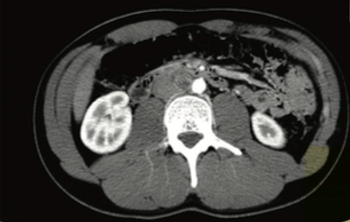

In this installment of Clinical Quandaries, Bendu Konneh, BS, and colleagues present a case of a 21-year-old male with a 4-month history of progressive swelling in the right testicle.